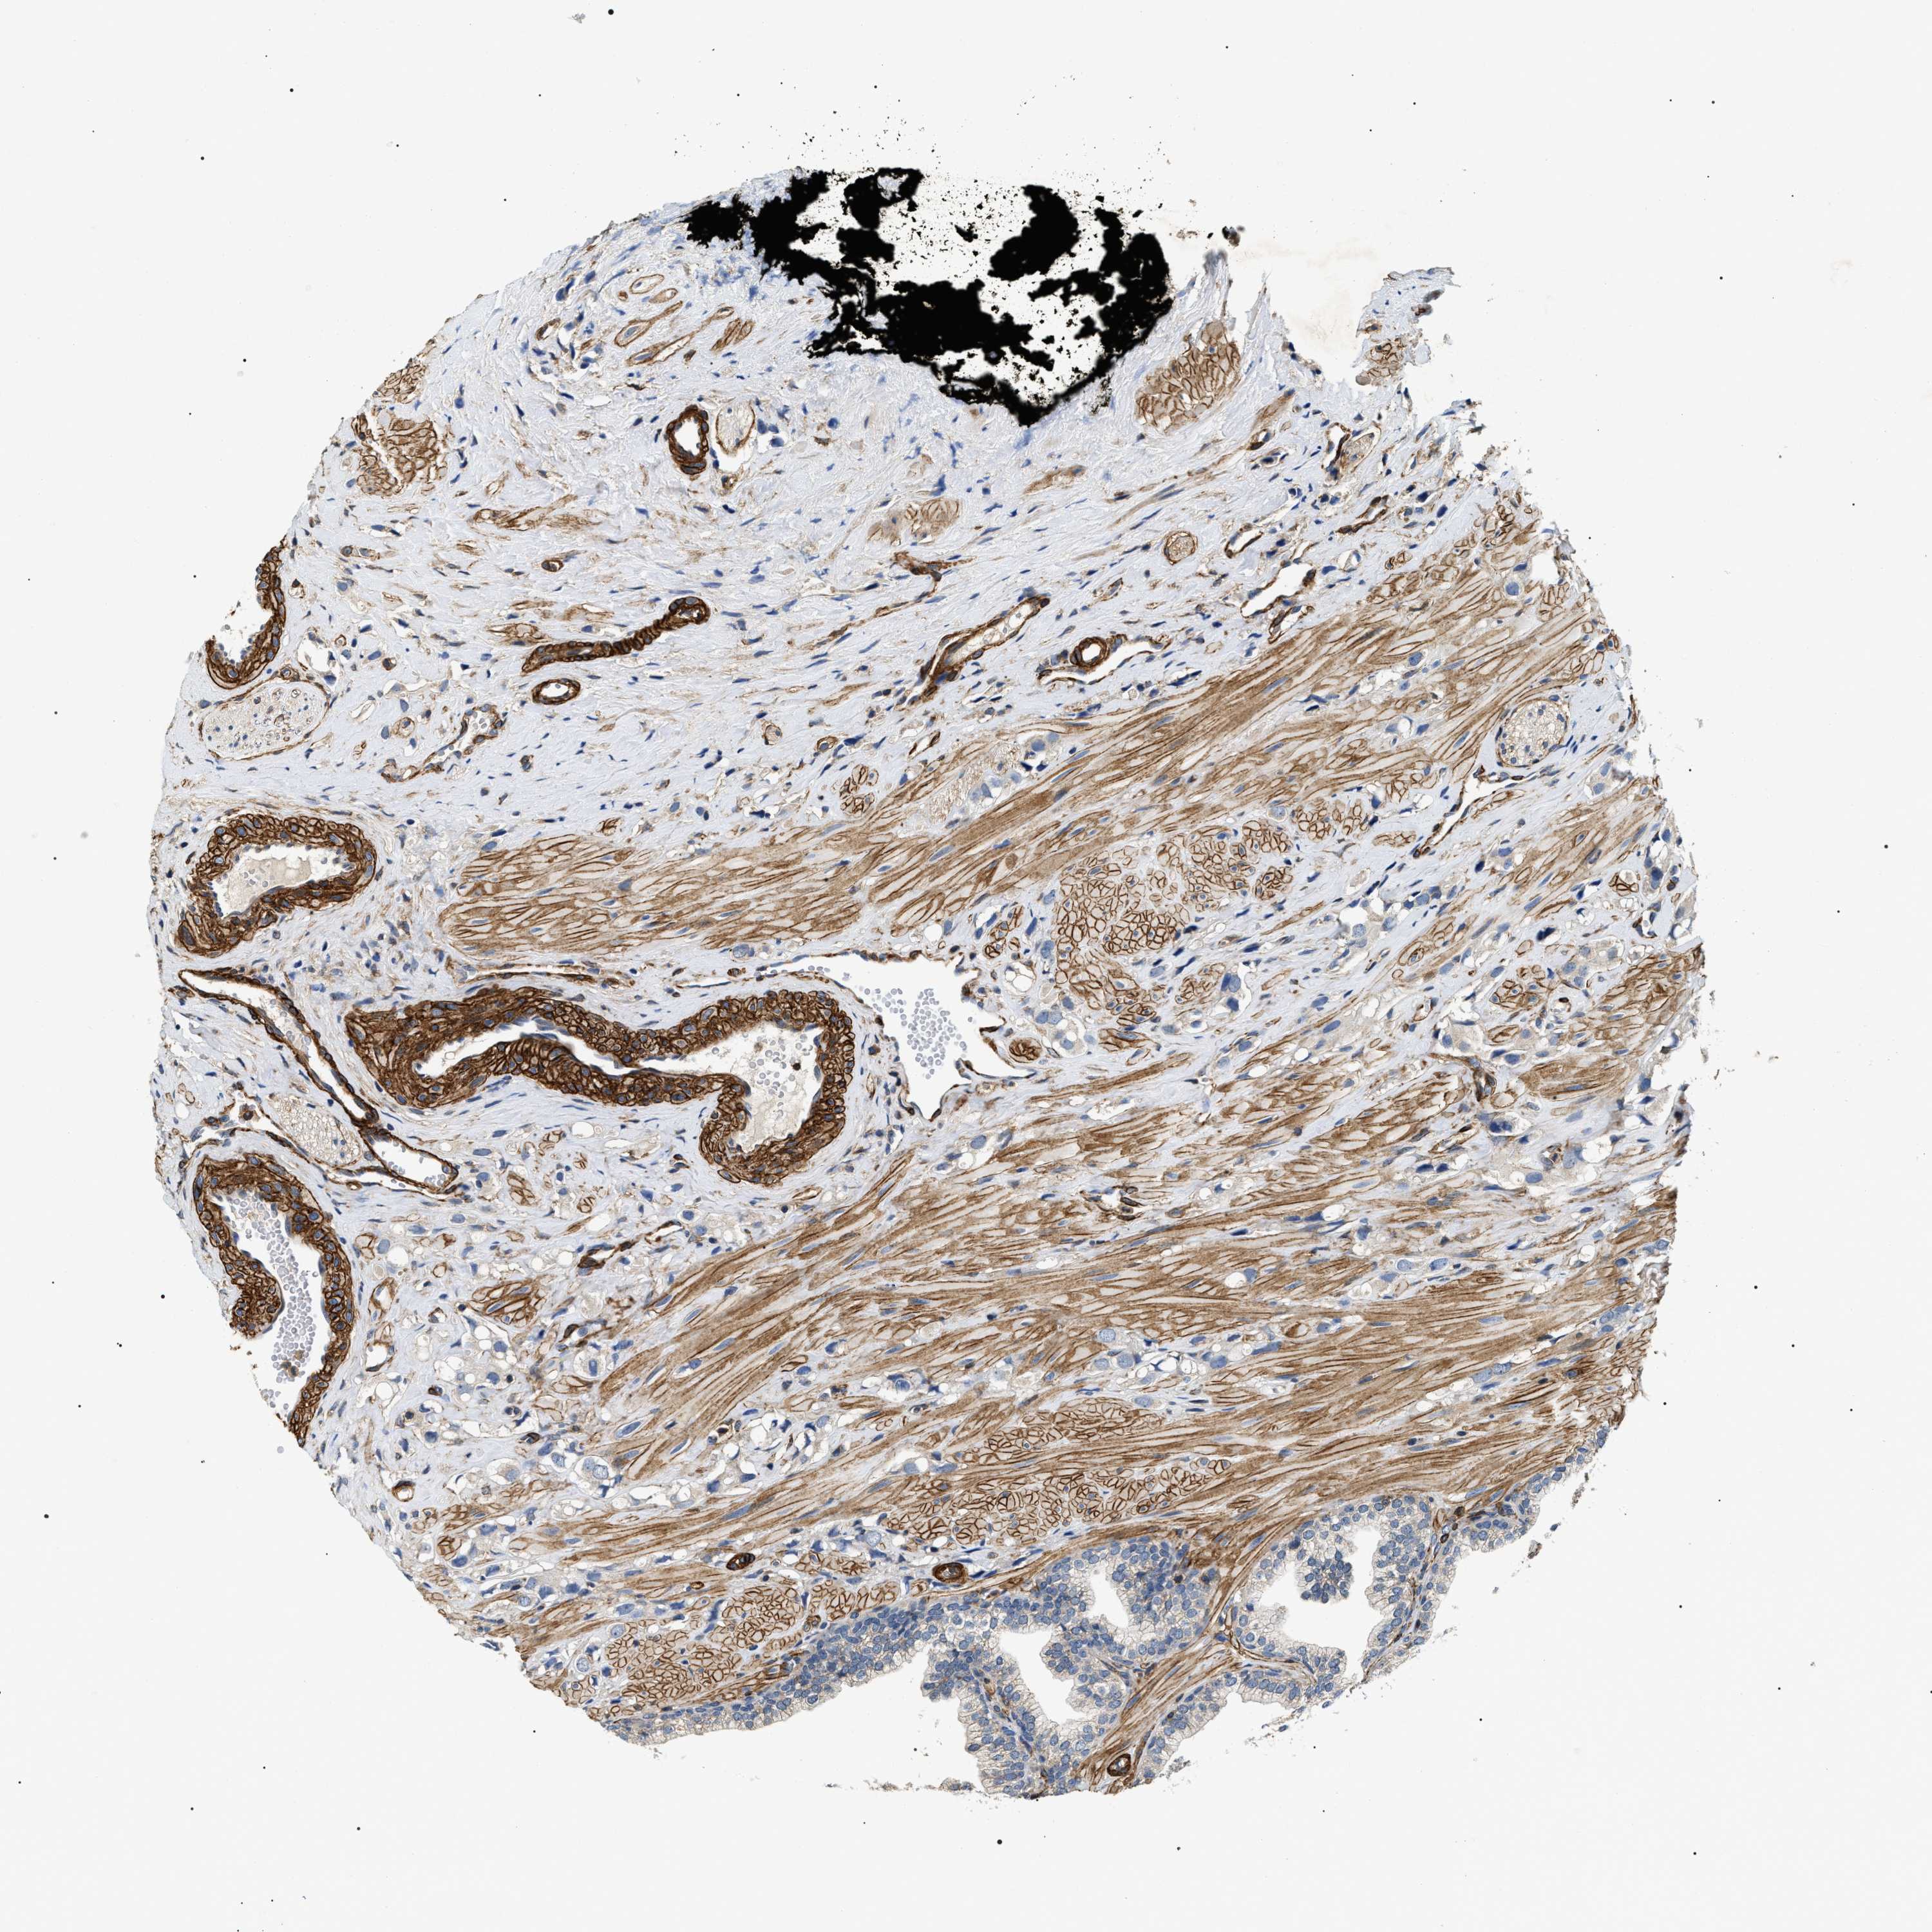

PROSTATE CANCER - Protein expressioni

A mouse-over function shows sample information and annotation data. Click on an image to view it in a full screen mode. Samples can be filtered based on level of antibody staining by selecting one or several of the following categories: high, medium, low and not detected. The assay and annotation is described here.

Note that samples used for immunohistochemistry by the Human Protein Atlas do not correspond to samples in the TCGA dataset.

Antibody stainingi

Antibody staining in the annotated cell types in the current human tissue is reported as not detected, low, medium, or high, based on conventional immunohistochemistry profiling in selected tissues. This score is based on the combination of the staining intensity and fraction of stained cells.

Each image is clickable and will lead to virtual microscopy that enables deeper exploration of all samples and also displays staining intensity scores, fraction scores and subcellular localization as well as patient and tissue information for each sample.

Antibody HPA020386

Staining

High

Medium

Low

Not detected

Intensity

Strong

Moderate

Weak

Negative

Quantity

>75%

75%-25%

<25%

None

Location

Nuclear

Cytoplasmic/membranous

Cytoplasmic/membranous,nuclear

Adenocarcinoma, High grade

Adenocarcinoma, Low grade